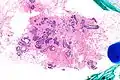

| Very low magnification micrograph of atypical ductal hyperplasia (ADH). The piece with ADH was circled by the pathologist with a marker, as it is so small, and sent for an additional opinion. H&E stain. | |

The name of the entity is descriptive of the lesion; ADH is characterized by cellular proliferation (hyperplasia) within one or two breast ducts and (histomorphologic) architectural abnormalities, i.e. the cells are arranged in an abnormal or atypical way.

ADH, cytologically, architecturally and on a molecular basis, is identical to a low-grade ductal carcinoma in situ (DCIS);[3] however, it has a limited extent, i.e. is present in a very small amount (< 2 mm).